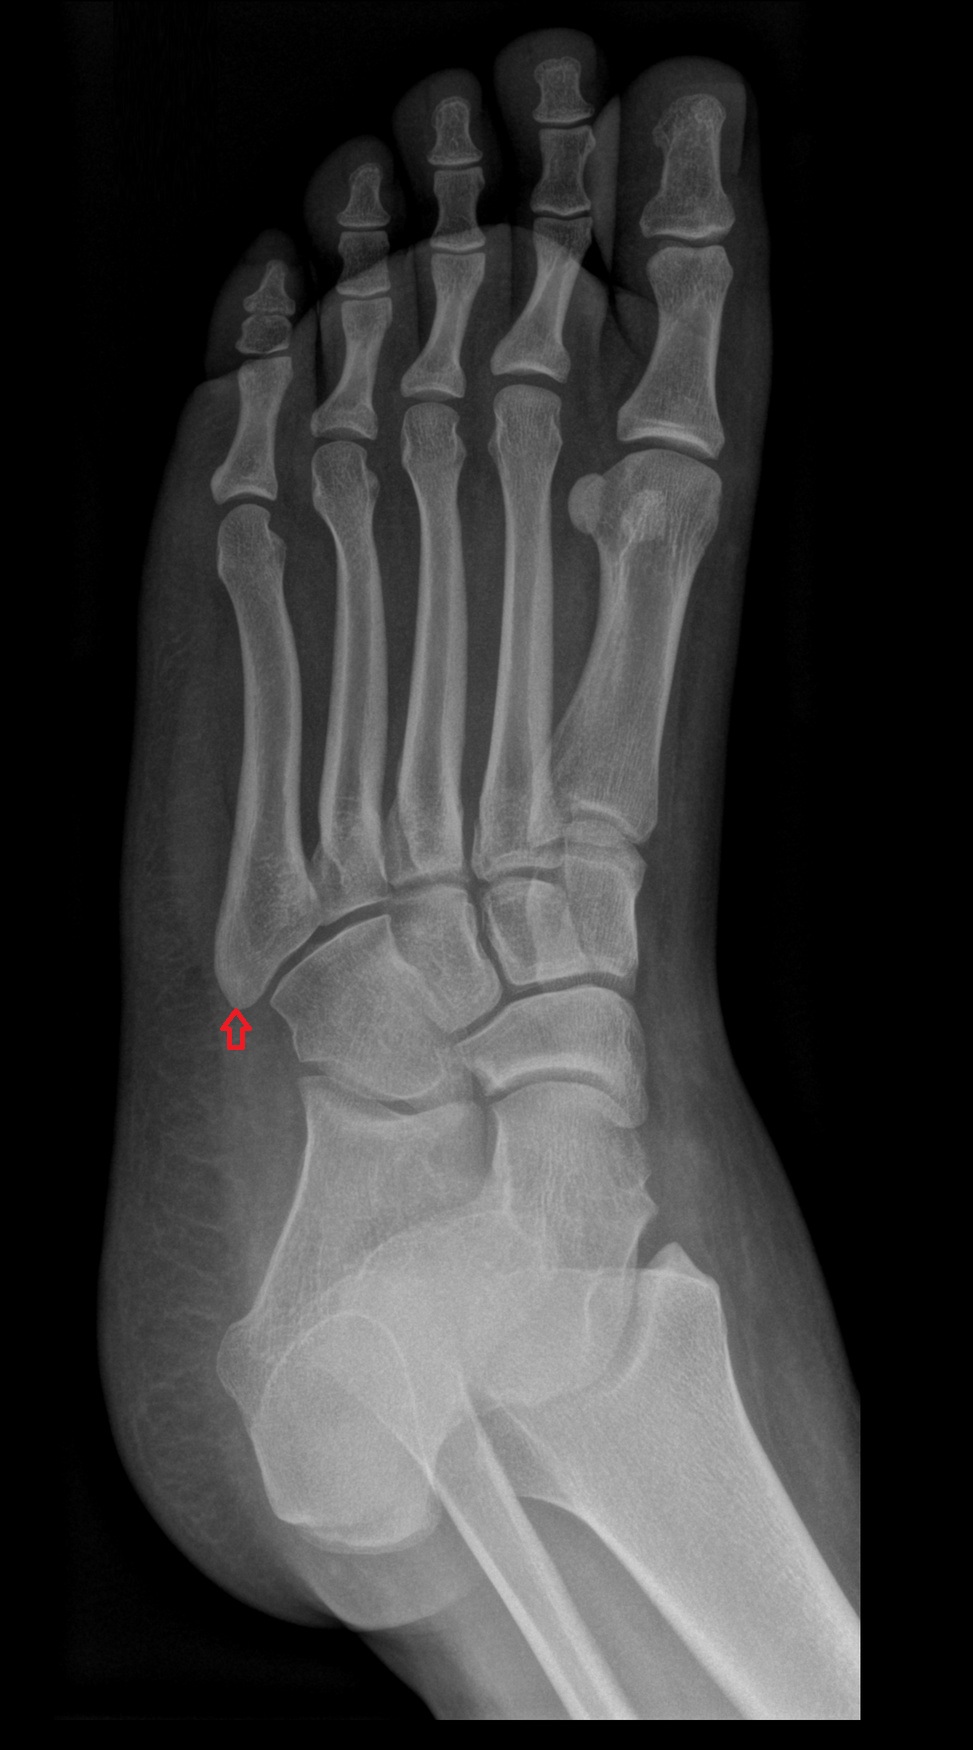

- Calcaneus

- Cuboid

- Ankle joint

- Talocalcaneal joint

- Talocalcaneonavicular joint

- Calcaneocuboid joint

- Cuneocuboid Joint

- Lateral cuneiform bone

- Medial cuneiform bone

- Intermediate cuneiform bone

- Navicular bone

- First metatarsal bone

- Second metatarsal bone

- Third metatarsal bone

- Fourth metatarsal bone

- Fifth metatarsal bone